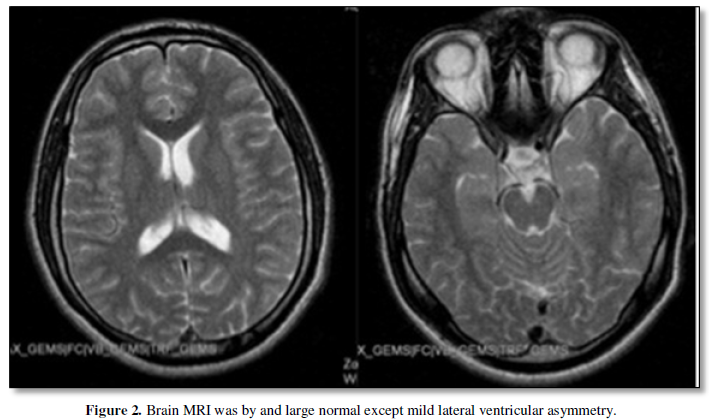

Twenty-three year-old male patient has mainly generalized tonic clonic seizures (GTCs) since the age of 15. Most of his seizures were nocturnal and happens several times a year. He does not describe myoclonic or absence seizures. His EEG shows 3-4 Hz generalized spike-and-wave discharges (Figure 1) and brain MRI was by and large normal except mild lateral ventricular asymmetry (Figure 2).